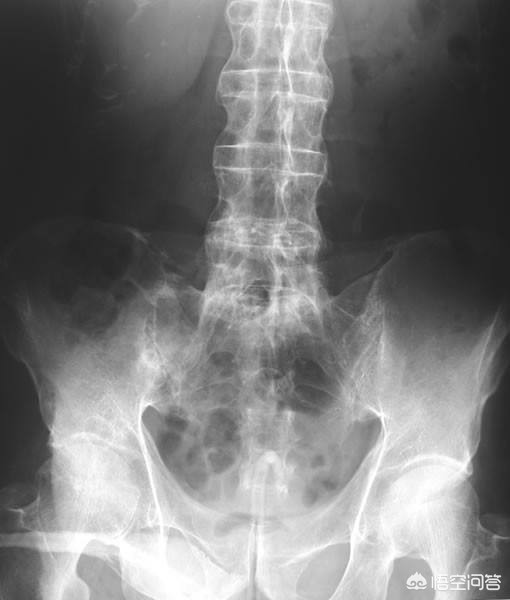

第二,x光检查与ct检查。很多强直性脊柱炎的患者,骶髂关节和脊柱已经发生了明显的炎症性的改变,尤其是有一些患者的腰椎和骶髂关节会出现明显的骨化和软骨的破坏。这种特征性的表现会在x光和ct上有所表现,尤其是当患者病情发展的比较严重、脊柱强直的比较明显的时候会出现一种特殊的x光表现,我们称之为竹节样改变。

结合患者的临床症状,x光或者ct的检查以及人类白细胞抗原的辅助,可以帮助医生诊断患者是否存在强直性脊柱炎。